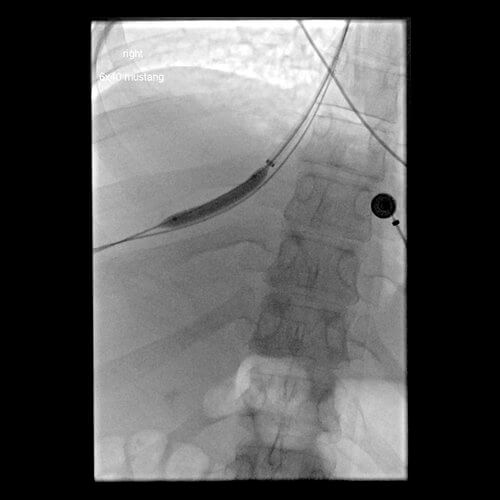

Comment: Attempts were made to place a TIPS in this patient from a hepatic vein approach. However, no recognizable hepatic veins were evident and no collaterals could be accessed percutaneously. As a result, we placed an 18g Chiba needle using a transhepatic approach from the midaxillary line; the needle was directed towards the RA-IVC junction. At the same time, the right internal jugular vein was accessed and a snare was positioned in the upper IVC. The needle was directed towards and passed through the snare. A guidewire was then advanced through the needle and that wire was pulled into the IJ sheath by the snare. A 5F sheath was then advanced from the liver into the IVC and a second wire was placed through the sheath and captured (in order to have a safety wire). At this point, the intrahepatic tract was dilated and a 10F sheath was advanced from the neck into this new tract through the liver. A CO2 venogram was then performed, followed by creation of a TIPS through this tract, extending from the right portal vein into IVC. Note that once the first stent was in place, it was short of the IVC so additional stents had to be placed. In addition, thrombus was noted at the origin of the right portal vein with preferential flow into the left portal vein. Mechanical thrombectomy had to be performed to insure portal vein and TIPS patency. At the conclusion of the procedure, the portosystemic pressure gradient decreased from 39 mm Hg to 10 mm Hg.